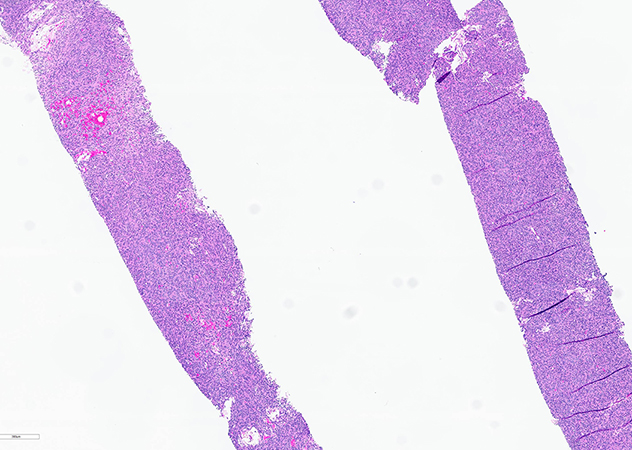

Clinical History: A 65-year-old male with a 10.5 pack-year smoking history (daily smoker) underwent a routine screening CT scan of the chest which showed a 10 cm mass in the right middle lobe of the lung. A CT-guided biopsy was performed (figures 1-3 H&E, 4-8 immunohistochemical stains) which showed a low-grade spindle cell neoplasm (figures 1-3). On immunohistochemistry, the spindle cells demonstrated immunoreactivity to AE1/AE3, p40, and CD20; a stain for TdT highlights the paucity of T cells (Figures 4-8). Also included in the workup were stains for S100, INSM1, STAT6, CD34, TTF-1, Napsin-A, PAX-8, Desmin, SMA, CD21, and SS18-SSX, which were all negative. Additional imaging and PET scan indicated that this mass was lobulated, heterogeneous, and partially calcified in the anteromedial middle lobe, abutting the pericardial surface and anterior pleura, further extending into the mediastinum. Whether this mass was primarily originating in the mediastinum and involving the lung or arising in the lung and extending into the mediastinal region was not clear at the time of the biopsy. Genomic DNA extracted from this tumor was analyzed using next-generation sequencing (NGS), which showed only KDM6A mutations.

The differential diagnosis for spindle cell neoplasms in the lung is wide, and includes epithelial as well as mesenchymal entities, both primary and metastatic. Particular care should be taken to exclude thymic origin. Helpful stains include pancytokeratin, p40, and CD20.References